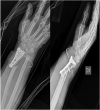

A peri-implant fracture near the volar plate of distal radius represent a very rare injury. The main factor of this lesion is high energy trauma on the wrist. We report a case of a 61-year-old woman with a peri-implant fracture located just proximally to the plate and a fracture of the ulnar head that occurred after a simple fall. The patient was surgically treated by plate and screws removal. The fracture was fixed using a longer volar plate for the radial fracture and a plate for the head ulnar fracture. Different factors such as osteoporosis, BMI and screw position could influence the fracture pattern. However, considering growing use of plates for distal radius fracture fixation, the frequency of these kind of fracture will probably increase.